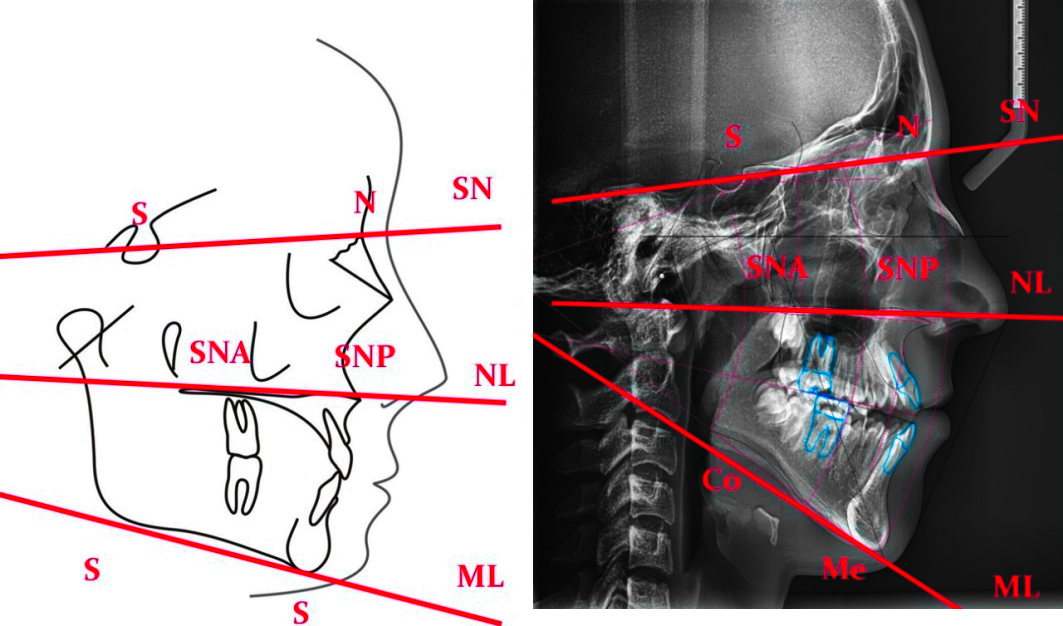

Для изучения боковых телерентгенограмм (ТРГ) пациентов с вертикальной дизокклюзией зубных рядов III степени проанализированы клинические карты пациентов ортодонтического отделения детской стоматологической поликлиники Ставрополя. Боковые ТРГ изучали по методу А.М. Schwarz, который основан на определении угловых и линейных величин черепа, их пропорциональности. Наиболее информативными для определения вертикальной дизокклюзии зубных рядов III степени являлись показатели углов SN-NL — показывает положение (наклон) основания в/ч по отношению к линии основания черепа (ретроинклинация < 8,5 (ортоинклинации) < антеинклинация), SN-ML — показывает положение (наклон) основания н/ч по отношению к линии основания черепа (антеинклинация < 32 (ортоинклинации) < ретроинклинация), NL-ML — межчелюстной угол косвенно показывает вертикальное соотношение оснований челюстей (горизонтальный тип роста < 23 — 28 < вертикальный тип роста) (см. рисунок).